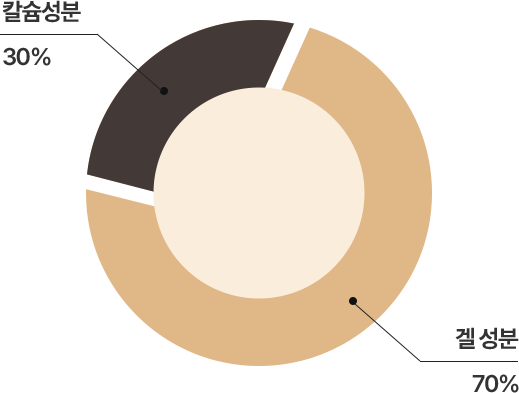

레디어스는 미네랄 성분(CaHA)과

겔 캐리어 입자들로 구성

천연 콜라겐의 생성을 촉진해

지속력이 향상

시간이 지남에 따라 겔 성분은 흡수되고

칼슘 성분의 미세한 입자들은 분해되어

결국 환자 본인의 천연 콜라겐만 남게됨